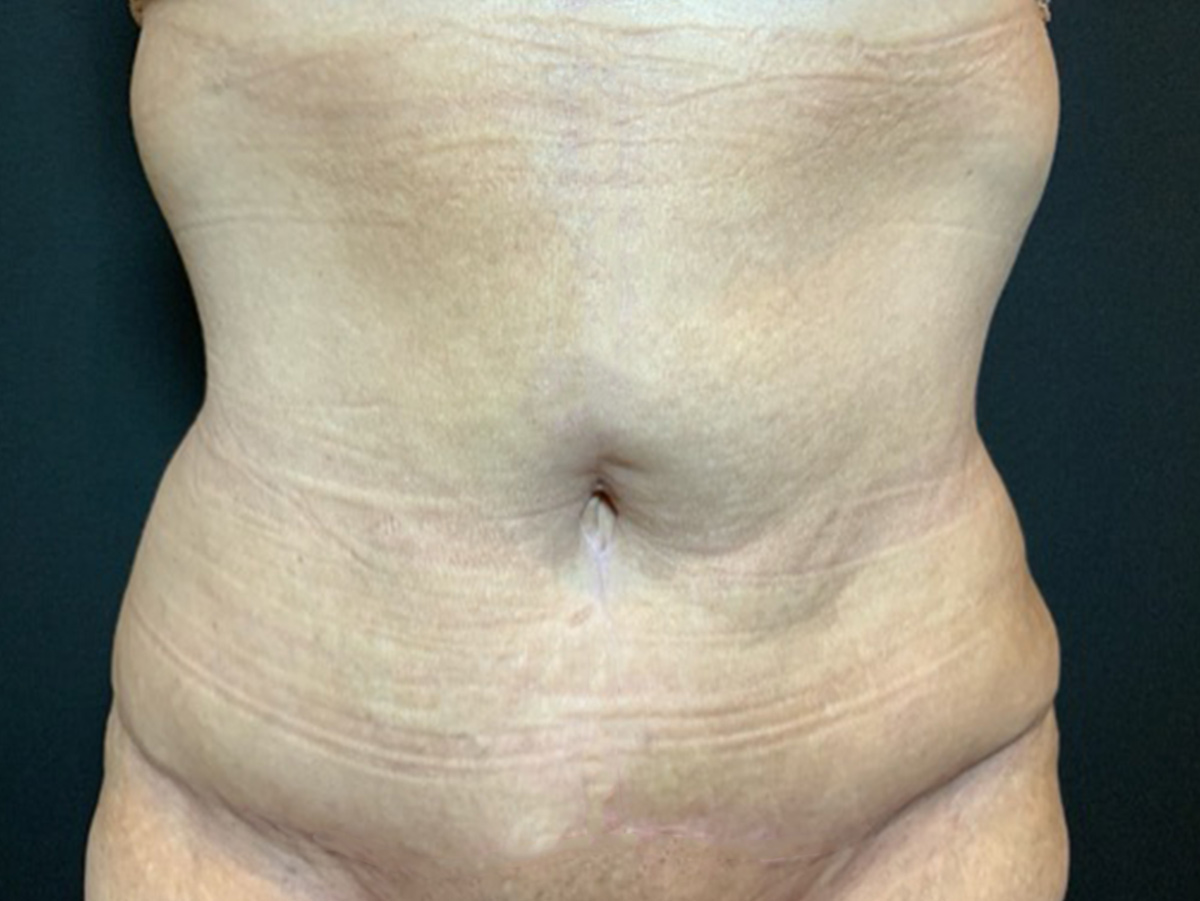

A Brazilian Butt Lift (BBL) produces a fuller, more shapely backside, without the visible scars associated with other body contouring procedures. The BBL is a popular choice, but patients often want to know what an enhanced derriere will cost them. In this blog, we’ll look at the cost of a Brazilian buttock lift, including factors […]